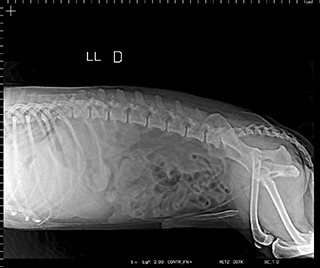

Radiologia Digital Direta / Digital Radiography

As radiografias geradas digitalmente podem ser transmitidas para iPad Apple®, notebooks e smartphones.

iPad com tela Retina Apple® possibilita a visualização das imagens com maior qualidade diagnóstica.

O treinamento aborda a geração das radiografias, a edição digital das imagens, e também a

escolha adequada de técnicas radiográficas como kilovoltagem, corrente elétrica e tempo de exposição.